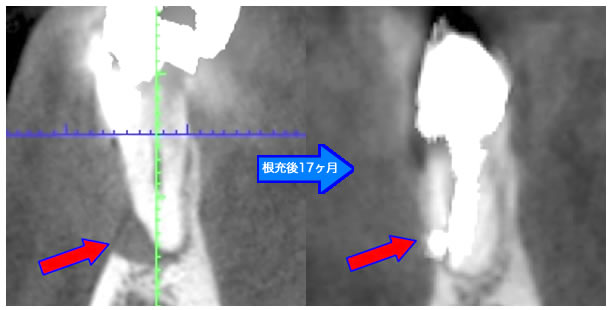

MTA根充後11ヶ月で透過像が消失し、根尖部が正常化しました。

頬側骨の喪失が見られましたが17ヶ月で回復しました。

頬側骨の回復が確認できます。

| 治療説明 | 左下第一小臼歯の頬側根尖部からの排膿、痛みはないそうです。X線画像では根尖部に透過像を認められます。 頬側の骨も失われており、歯髄が死んだことが原因と考えられます。修復物を除去後根管治療を行い、根管充填後、透過像は消失、頬側骨も再生されていました。 |